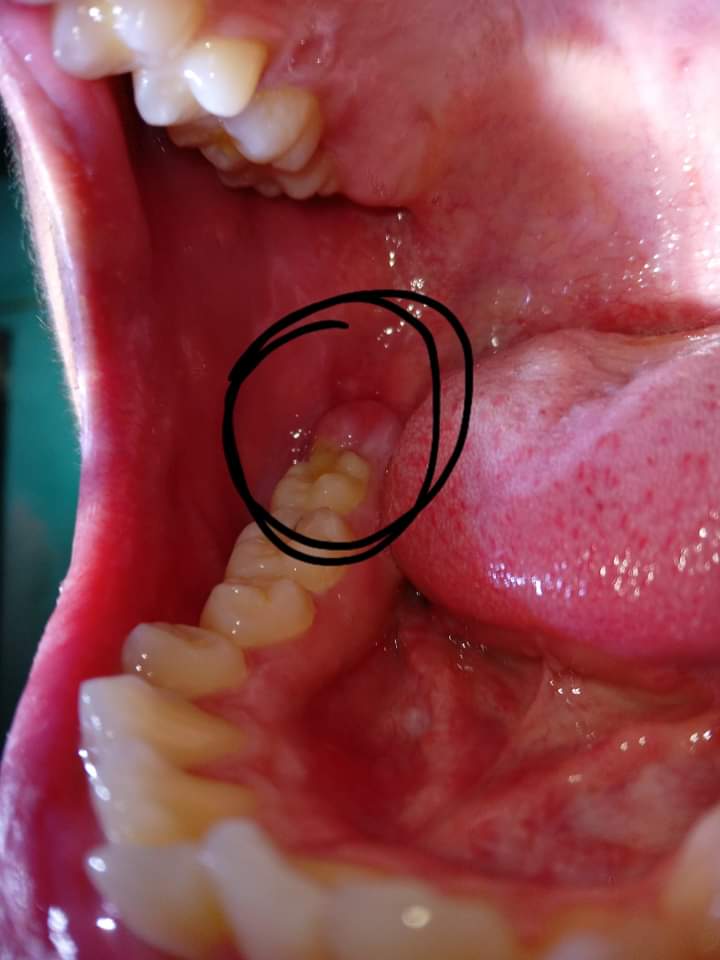

Em có nhổ răng khôn vào hồi t2.Sau 1th thì gần vị trí răng khôn đã nhổ có xuất hiện 1 nốt phồng ,khi ấn vào thì thấy có dịch màu ngà vàng chảy ra.Em cs súc miệng nc muôia thì có thấy nốt đó teo dần.Nhưng hôm sau cx ở vị trí răng khôn cs 1 nốt nhỏ mọc lên nốt này thì lại cứng,nhỏ.Với tình trạng lợi của e dạo này rất mỏng,có thể thấy đc luôn cả xương or hàm răng.Kbt đây là tình trạng gì nhờ bác sĩ giải đâp ạ.

Cái nốt phồng trong ảnh bây h bé lại rồi nm lại mọc 1 nốt mới ở gần đó nốt này cứng và chắc hơn nốt phồng này( nốt phồg này mềm ko đau ko cứng có dịch ngà vàng) thì bị sao ah